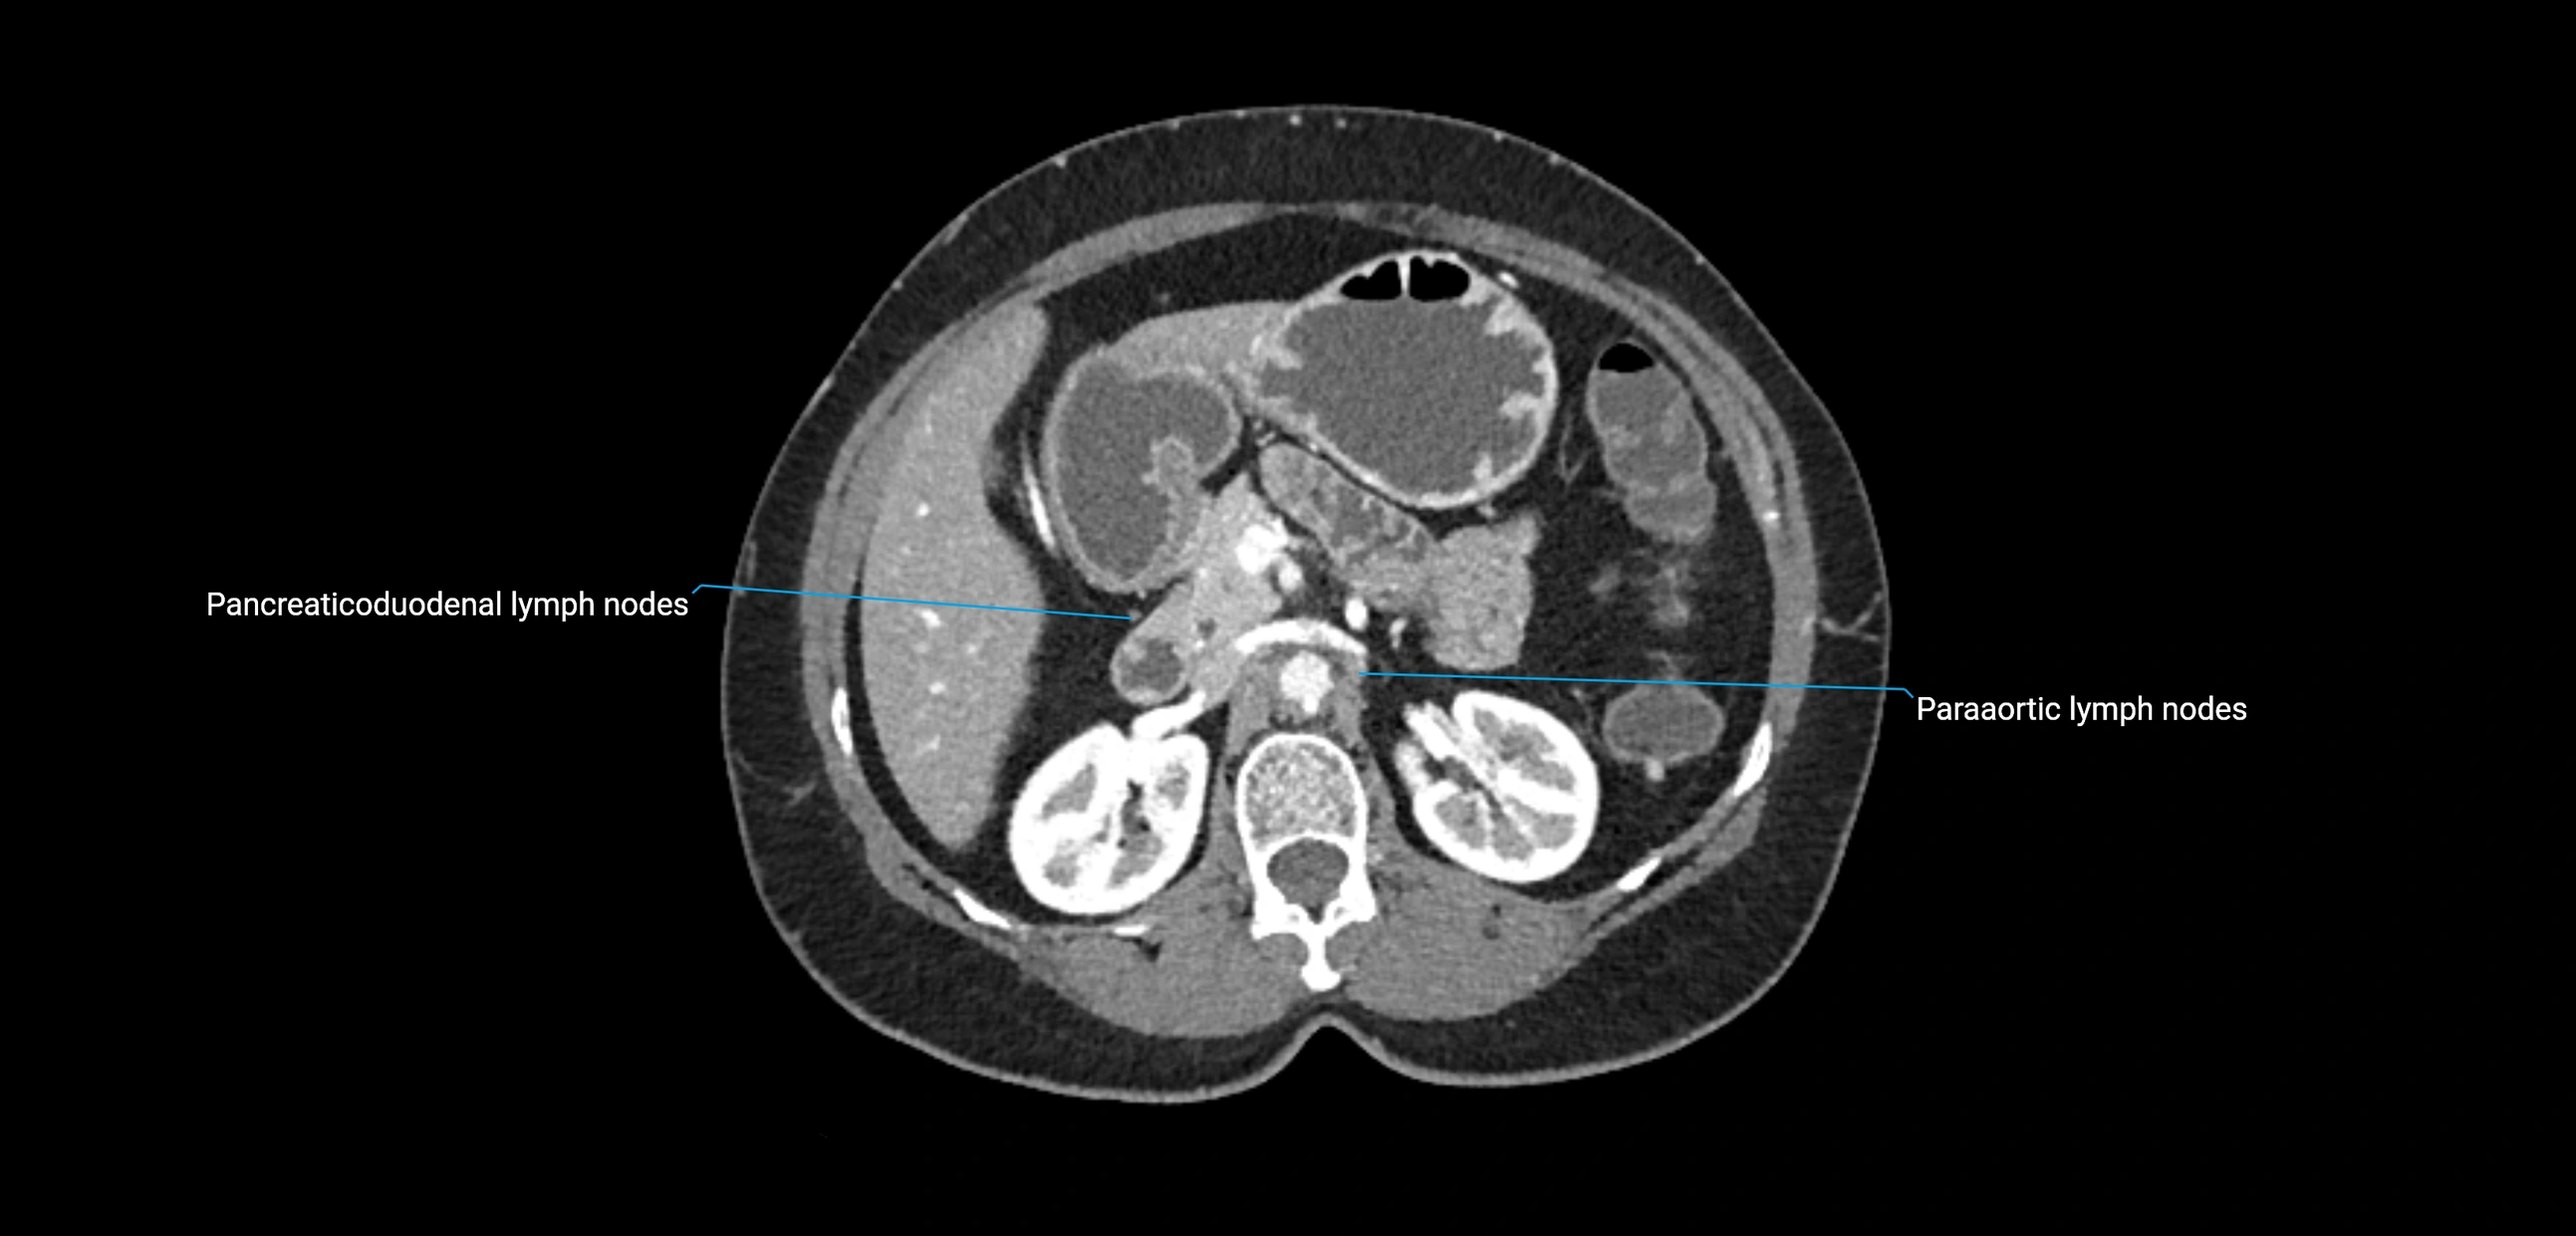

CT Appearance

CT Pre-Contrast:

• Nodes appear as soft-tissue density nodules adjacent to the aorta and IVC

• Calcification may be seen in chronic infections (e.g., tuberculosis)

CT Post-Contrast:

• Normal nodes enhance homogeneously

• Malignant nodes may show heterogeneous enhancement, central necrosis, or conglomerate formation

• Size >1 cm short axis is suspicious, though morphology and distribution are equally important

CT image

image